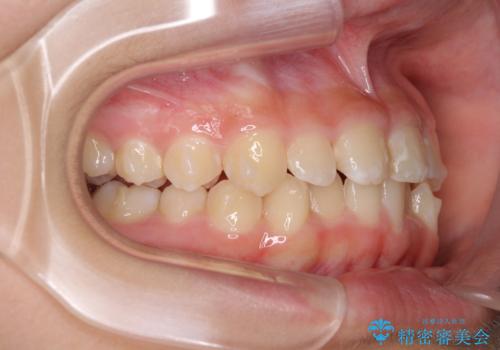

上顎骨の幅が下顎骨よりも小さいので、拡大装置により骨幅を広げて上下関係を改善し、その後インビザラインにて歯並びを整えることとしました。

上下の骨幅を改善したことで、スムーズに歯列矯正を行うことができました。